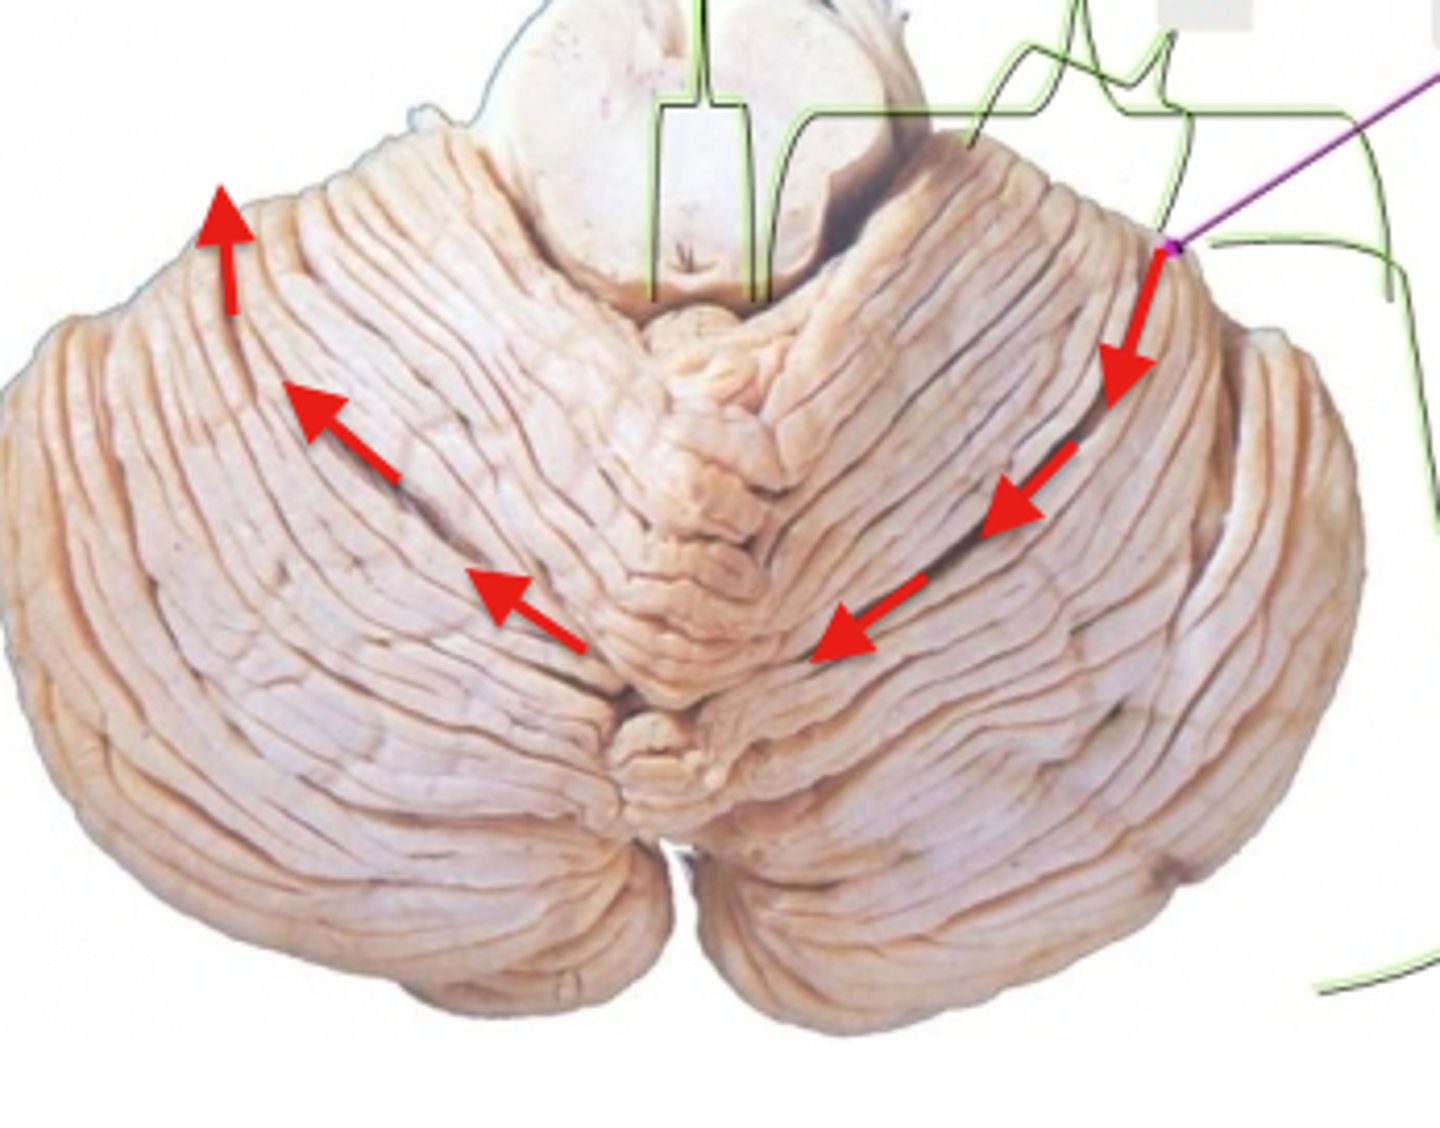

Cerebellum

anterior lobe of cerebellum

posterior lobe of cerebellum

vermis

cerebellar peduncles

folia

arbor vitae

Primary fissure